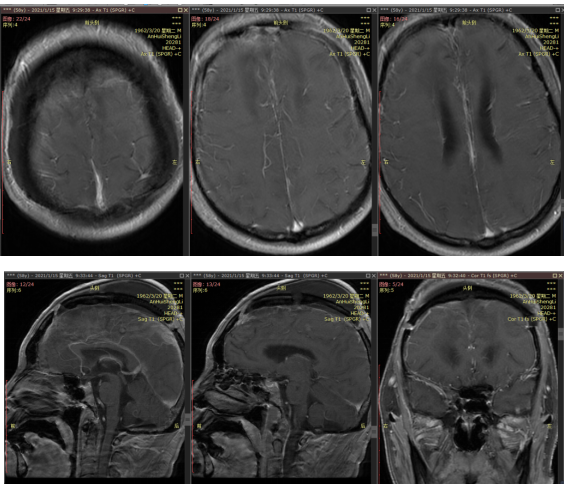

这不知道是23床患者汪XX第多少个危急值了。从2020.12.12患者急诊入院开始,颅底及脑干肿瘤亚专科全体医护人员就知道有一场硬仗要打。因为即使已经在神经外科工作多年的护士,也极少见到如此巨大的双额中央区窦镰旁脑膜瘤,肿瘤10.4cmX6.1cmX4.1cm大小。大家还清晰地记得曾有2位外省慕名来颅底及脑干肿瘤亚专科手术成功的侵犯矢状窦的脑膜瘤患者,一位患者来自云南昆明,在当地医院术前谈话之后因手术风险来我科治疗;另一位患者来自福建,因在当地医院2次术后复发,再辗转多家医院而来我科就诊,他们肿瘤最大径分别为3cm、6cm。眼前这位汪先生入院时全身状况很差,巨大肿瘤已导致昏迷,除右上肢刺痛能活动外,其余肢体几乎无反应,而且带入多处压疮,尤其是骶尾部不可分期压疮,面积10cm*7cm,清创后伤口深达2cm,让不少护士都深吸了一口凉气。

术前

术后

入院后医护人员立即为患者进行术前准备,亚专科主任夏成雨教授制订了精心周密的手术方案,周日急诊予以手术到凌晨,历时12小时,肿瘤成功全切除,患者进入病区的监护病房严密监护。心电监护、呼吸功能监测、体温监测、神经系统功能评估、心功能监测、电解质水平监测……,监护病房的十几名护士在护士长及护理组长的带领下,与夏成雨教授一起商讨护理方案。术后第一天查房,夏成雨教授即和护士说:这个患者虽然手术顺利,术后复查头颅CT显示颅内情况也很好,无明显出血、水肿等副损伤,但术后治疗任务艰巨,最艰苦的是护理,因为患者长期营养不良,术前即昏迷、瘫痪合并压疮。最大的威胁是压疮,病菌随时通过压疮面进入机体,危及生命,肺部感染和压疮感染难以避免。为了更好地进行压疮护理,护士长请来院内国际伤口造口师指导压疮换药;与营养科联系,制订患者的营养计划;请康复科会诊,制订早期康复方案。